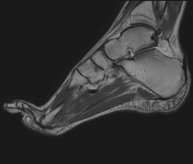

Exploració per estudiar aquesta articulació i les lesions freqüents de lligaments (esquinços), així com l'afectació d'altres estructures, com el cartílag o l'os. També és de gran utilitat per diagnosticar alteracions al tendó d'Aquil·les (tendinitis o trencaments). La durada aproximada és de 20 minuts. No utilitza radiació ionitzant. - RM de Peu

Exploració per a l'estudi de lesions en tendons, músculs i petites articulacions. Permet valorar amb eficàcia les lesions al cartílag. També és de molta utilitat per completar l'exploració ecogràfica prèvia. No empra radiació ionitzant. Té una durada aproximada de 20 minuts. - Artro-RM Hombro